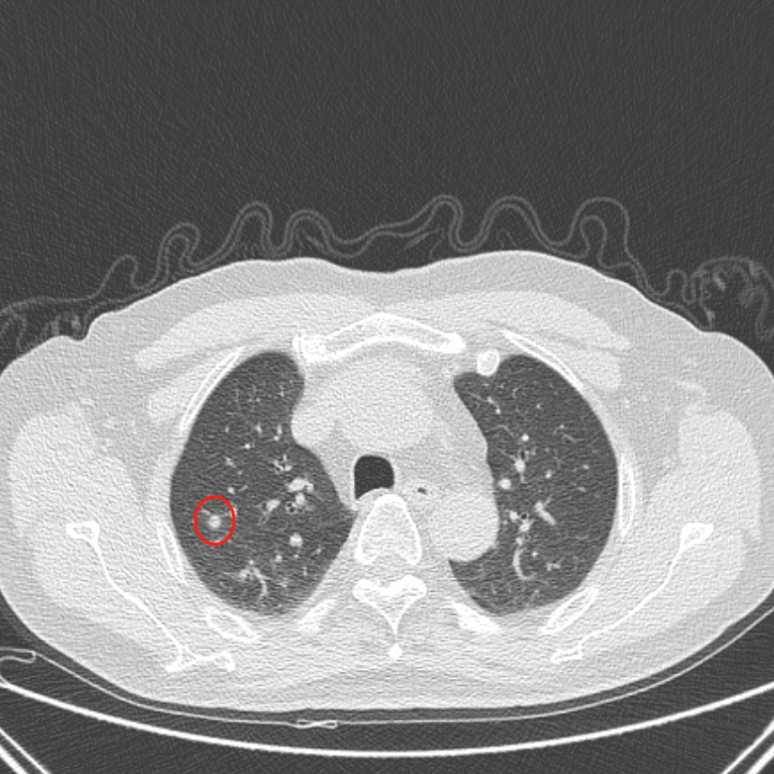

消融后,晕征范围完全覆盖结节位置